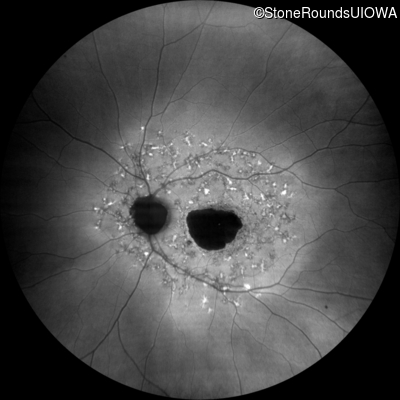

Age at visit: 52 years

This 52 year old man first noticed reduced visual acuity at age 21.

Age at visit: 54 years

Age at visit: 59 years